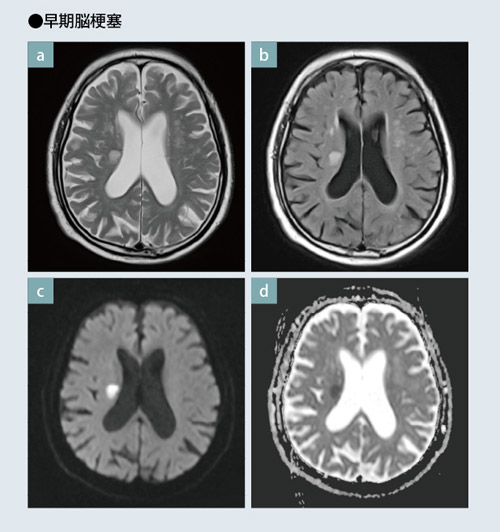

専用 脳MRI 3 高性能MRI(1.5テスラ)|施設・設備|おおたけ脳神経・漢方内科の詳細情報

高性能MRI(1.5テスラ)|施設・設備|おおたけ脳神経・漢方内科。今回導入された3T-MRIについて|名古屋セントラル病院。1.5T MAGNETOM ESSENZA 頭頸部領域における質の高い診断と検査。

「脳MRI3」

MRI | 三島総合病院 | 地域医療機能推進機構